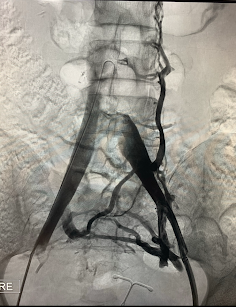

Antes: Oclusión bilateral ilíaca

Antes

Oclusión de ambas venas ilíacas/Sindrome de congestión pélvica

Después: Reconstrucción con stents

Después

Reconstrucción con stents. Flujo normalizado y resolución clínica.